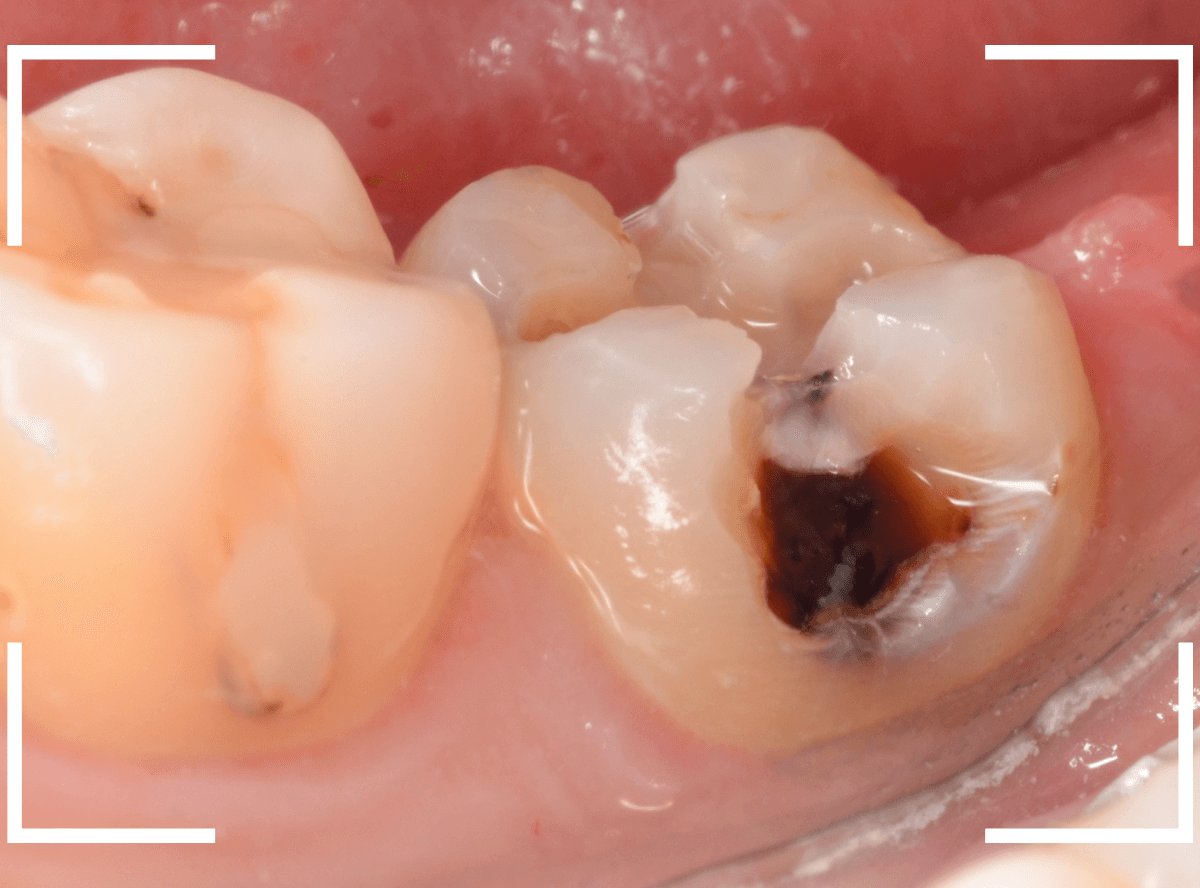

Case.10 レントゲンに写らない側面の虫歯を、少しずつ削って調べる

こちらも、虫歯が歯のあちこちで進行してしまっている患者さんのケースです。

特に側面の虫歯が深そうです。

側面にできた虫歯はレントゲン写真では診断しづらくやっかいです。

今回は「見るからに深そう」ですが。

さすがにレントゲン写真でも虫歯がありそうな事は確認できますが、実際にどうなってるのかはあまりはっきりわかりません。

少しずつ虫歯を除去していきます。

歯の側面から、手前の歯までつながった虫歯になっていました。

手前の歯までの虫歯を除去しました。

歯の後ろ側の側面も、大きな虫歯になっていますので、処置します。

隣の歯との間(隣接面)は、中で虫歯が広く進んでることが多いです。

結局、前後の歯に渡る広い虫歯でした。

レントゲン写真だけでは、ここまでの虫歯は判断できませんでした。